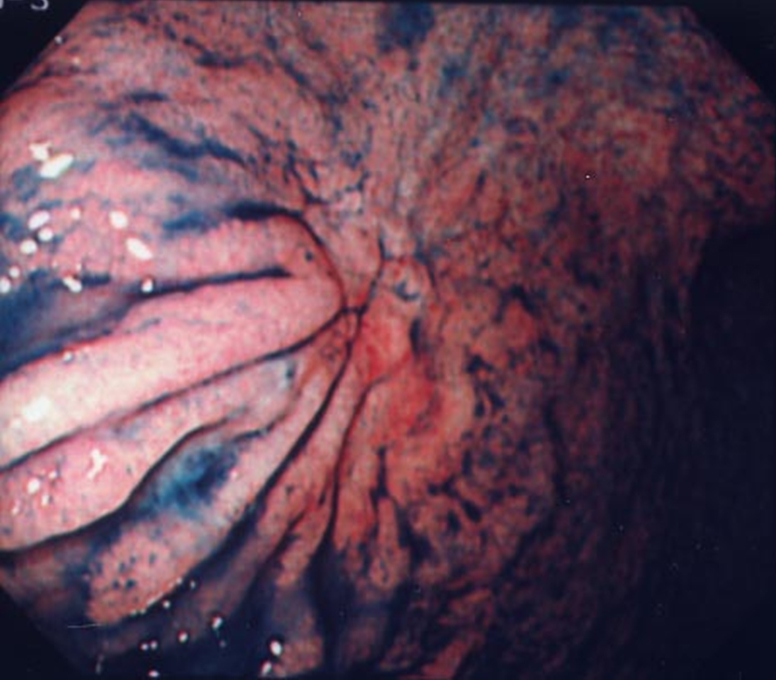

上部消化管内視鏡検査所見:食道胃静脈瘤は認めなかった.胃角部前壁にひだの融合と棍棒状変化を伴う0-IIc病変を認めた.深達度はSMと診断した(Fig. 2).生検結果は低分化腺癌であった.

Endoscopic findings: 0-IIc lesions with folds and rod changes in the anterior wall of the stomach. The biopsy result was poorly differentiated adenocarcinoma.